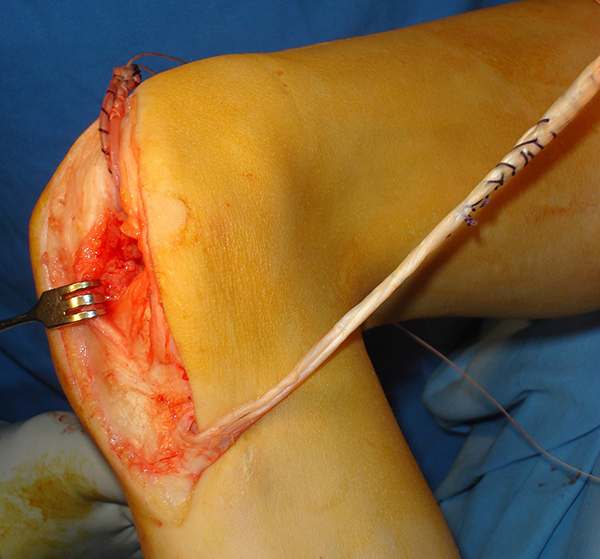

Posteriormente se procede a pasar el extremo libre del semitendinoso a través de la articulación saliendo posteroexterno en el cóndilo externo en posición a lo alto (over the top), y luego de rodear el cóndilo se dirige anterior y distal en dirección al tubérculo de Gerdy por la cara lateral de la rodilla. La fascia lata se pasa en sentido inverso siguiendo el mismo recorrido, de posteroexterno hacia anterior, rodeando el cóndilo externo pasando luego intraarticular se extrae en la cara anterior de la tibia (fig. 7). Se procede a tensar ambos extremos tratando de llegar a la máxima extensión posible de la rodilla, pero controlando y evitando la luxación anterior de la tibia sobre el fémur (fig. 8).

Figura 7: Pasaje del injerto de fascia lata de posteroexterno y su salida luego de pasar por la articulación en la cara anterior de rodilla.